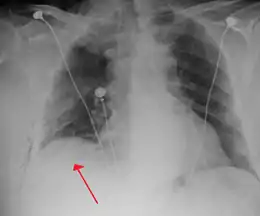

Chest X-ray

A plain chest radiograph, ideally with the X-ray beams being projected from the back (posteroanterior, or "PA"), and during maximal inspiration (holding one's breath), is the most appropriate first investigation.[30] It is not believed that routinely taking images during expiration would confer any benefit.[31] Still, they may be useful in the detection of a pneumothorax when clinical suspicion is high but yet an inspiratory radiograph appears normal.[32] Also, if the PA X-ray does not show a pneumothorax but there is a strong suspicion of one, lateral X-rays (with beams projecting from the side) may be performed, but this is not routine practice.[15][19]

It is not unusual for the mediastinum (the structure between the lungs that contains the heart, great blood vessels, and large airways) to be shifted away from the affected lung due to the pressure differences. This is not equivalent to a tension pneumothorax, which is determined mainly by the constellation of symptoms, hypoxia, and shock.[13]

The size of the pneumothorax (i.e. the volume of air in the pleural space) can be determined with a reasonable degree of accuracy by measuring the distance between the chest wall and the lung. This is relevant to treatment, as smaller pneumothoraces may be managed differently. An air rim of 2 cm means that the pneumothorax occupies about 50% of the hemithorax.[15] British professional guidelines have traditionally stated that the measurement should be performed at the level of the hilum (where blood vessels and airways enter the lung) with 2 cm as the cutoff,[15] while American guidelines state that the measurement should be done at the apex (top) of the lung with 3 cm differentiating between a "small" and a "large" pneumothorax.[33] The latter method may overestimate the size of a pneumothorax if it is located mainly at the apex, which is a common occurrence.[15] The various methods correlate poorly but are the best easily available ways of estimating pneumothorax size.[15][19] CT scanning (see below) can provide a more accurate determination of the size of the pneumothorax, but its routine use in this setting is not recommended.[33]

Not all pneumothoraces are uniform; some only form a pocket of air in a particular place in the chest.[15] Small amounts of fluid may be noted on the chest X-ray (hydropneumothorax); this may be blood (hemopneumothorax).[13] In some cases, the only significant abnormality may be the "deep sulcus sign", in which the normally small space between the chest wall and the diaphragm appears enlarged due to the abnormal presence of fluid.[16]